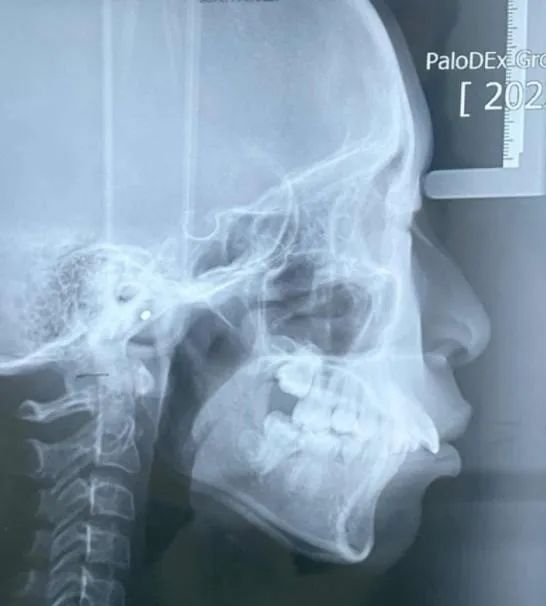

这位小朋友主诉牙不齐,嘴突,没下巴,来面诊时刚刚结束替牙期,正处于年轻恒牙列,生长发育高峰期。

根据牙片资料和口内检查发现骨性,上前牙唇倾,lll度深覆盖,上下颌牙弓狭窄,右下4左下5先天缺失,上颌轻度拥挤,下颌牙齿散在间隙,颏唇沟较深,闭唇时颏肌紧张。

可以看到佩戴4个月的时候,孩子的牙齿和面型有了不错的变化,上下颌牙套贴合,双侧兔子皮筋二类牵引佩戴良好。

牙齿矫正14个月后,上下颌中线对正,上下牙齿排列整齐,牙弓卵圆形,上下牙弓匹配,前牙达到正常覆合覆盖,牙齿尖窝关系良好。

从牙片资料看上下前牙内收直立,颌平面整平,上颌内收,前牙达到正常覆合覆盖,颏部前伸良好。